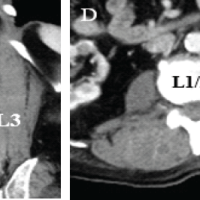

We present a case of a 68-year-old gentleman, a known epileptic for the past 15 years. Following a significant epileptic episode, he encountered abrupt and intense pain in both hip joints while in bed during the night. Subsequent to the episode, he found himself unable to mobilize or elevate his legs. A subsequent examination by his family physician the following morning prompted a portable X-ray, which suggested bilateral femoral neck fractures. The patient, under consistent anti-epileptic therapy (Tab Eptoin-Phenytoin and Tab Levera-Levetiracetam) for the past 15 years, had been seizure-free for the preceding 12 years. Approximately 3 months before the incident, a neuro-physician, assessing his condition, conducted an EEG with normal results, recommending a discontinuation of medication. On general examination, evidence of a tongue bite indicated a seizure during sleep. Although his MRI brain exhibited age-related atrophy without significant pathology, he was referred to our orthopedic department for further management. At the time of presentation, the patient was conscious, cooperative, and well orientation, with both limbs in adduction and external rotation. He experienced tenderness in the groin and significant pain on movement of both the hips, with no neurological or vascular deficits. Pelvic AP radiographs revealed Garden type IV transcervical neck of femur fractures with comminuted greater trochanter fractures in both hips. Despite having no previous hip pain and an active lifestyle, maintaining full functionality with weight-bearing. The severe displacement of hip fractures, delayed presentation, combined with his age and quality of bone, led us to anticipate a failure of osteosynthesis. Consequently, we planned bilateral total hip replacement surgery. Following thorough counseling with the patient and his family, staged bilateral hip replacement surgeries were proposed. Femur canal was Dorr B type, and pre-operative templating and planning led to the selection of uncemented prostheses (although cemented implants were kept backup) with a Ceramic on Poly bearing [3]. Comminuted fractures of the greater trochanter on both sides were addressed using two Tension band wires and non-absorbable supplementary Ethibond no. 5 sutures. The surgical procedure involved an anterolateral approach, utilizing a 32mm diameter head for the Pinnacle Poly constrained acetabular liner with a 50 mm outer shell diameter (DePuy, Warsaw, IN, USA) and a size 15 Corail cementless stem in the left hip. Subsequently, after a 5-day interval, the right hip underwent a similar procedure with similar implants. Both intraoperative and post-operative periods transpired without complications. Fig 2.

In adults with normal bone structure, the occurrence of bilateral femoral neck fractures is an infrequent phenomenon, typically necessitating substantial external force such as a motor vehicle accident or a fall from a considerable height [1]. While violent muscle contractions during seizures are recognized to cause fractures or dislocations, with an incidence of 1.1% following a convulsion [2], the musculoskeletal consequences of seizures extend beyond the conventional posterior shoulder dislocation. However, there are notably scarce documented cases of bilateral hip fractures occurring during seizures [4,5]. Literature underscores that individuals with epilepsy face an elevated fracture risk, with an increased likelihood of two- to six-fold [6]. Notably, certain anti-epileptic drugs, particularly Phenytoin, are known to alter calcium metabolism, potentially inducing osteomalacia or reducing bone density during prolonged treatment. This elevates the susceptibility to pathological fractures, emphasizing the importance of monitoring bone mineral density in patients using anti-epileptic drugs [7]. Our patient, under long-term anti-epileptic therapy, had been receiving Vitamin D and calcium supplements, with initial values on admission indicating a Vitamin D level of 26.6 and a calcium level of 8.9. Histopathological examination of the femoral head specimen revealed normal bone histology. Recommendations by Pack et al advocate for Vitamin D and calcium supplementation, alongside vigilant monitoring of bone mineral density, especially in individuals undergoing prolonged antiepileptic treatment, particularly if they present with concurrent bone pathologies [8]. For patients under the age of 60, internal fixation of femoral neck fractures represents the standard of care, while arthroplasty procedures tend to be reserved for the elderly population or specific clinical scenarios [9,10]. In cases where inadequate reduction is achieved following femoral neck fractures, the risk of osteosynthesis failure becomes particularly concerning. However, the current evidence base has not established a definitive correlation between the timing of fixation and the subsequent development of osteonecrosis of the femoral head [11]. Duckworth et al. have identified a direct association between comorbidities compromising bone quality and fixation failure in displaced femoral neck fractures among the young adult demographic. Their findings suggest individuals over 40 years exhibiting compromised that bone integrity may warrant consideration for primary total hip arthroplasty given the heightened predisposition to fixation failure [12]. For this particular patient, the decision to undertake staged uncemented bilateral constrained total hip arthroplasties using anterolateral approach was predicated on several key considerations: The patient’s chronological age, the presence of an epileptic disorder, the prospective risk of developing post-operative aseptic osteonecrosis of the femoral heads, and the anticipated necessity for future revision procedures. It warrants highlighting that the rates of instability and dislocation following total hip arthroplasty undertaken for femoral neck fractures notably surpass those encountered in arthroplasty procedures performed for the treatment of degenerative osteoarthritis [15]. This risk is further compounded in patients with recurrent seizure disorders. Primary total hip arthroplasty in the setting of cognitive deficits or neuromuscular diseases has been associated with notable post-operative dislocation rates; hence, constrained liner or dual mobility hip arthroplasty is recommended in such cases [16,17]. In our surgical approach, we employed anterolateral exposures to circumvent violation of the posterior capsule and musculature, thereby mitigating dislocation risk [18-20]. Moreover, the utilization of constrained acetabular liners aimed to confer stability is a pivotal consideration in patients with a history of recurrent dislocations. Constrained acetabular components, renowned for their efficacy in preventing instability without substantially compromising implant longevity, were judiciously selected to optimize the durability of the arthroplasty constructs [21,22]. (Fig 3 & 4).